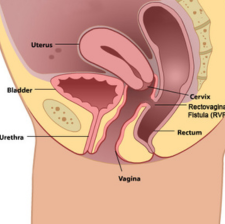

Recto Vaginal Fistulas

Rectovaginal fistulas are abnormal epithelial-lined connections between the rectum and vagina. They can be quite bothersome to both the patient and the surgeon due to their irritating and embarrassing symptoms and high failure rate after repair.

Recto Vasical Fistulas

Rectovesical fistula (RVF) is defined as an abnormal communication between the rectum and the urinary bladder, most commonly after an iatrogenic injury during pelvic surgery. Patients with RVF may have various clinical presentations, ranging from fecaluria,